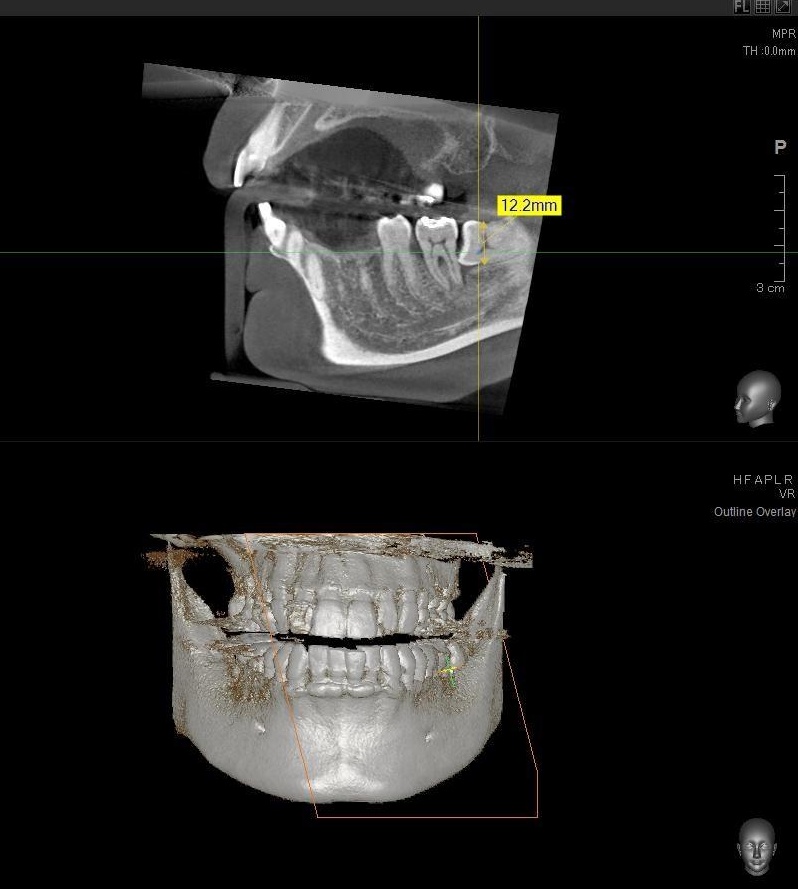

さらに、下顎の親知らずは下歯槽神経に非常に近いところに生えている場合もあるため、CTも撮影し詳しい解析を行います。

親知らずが生えている位置が、神経に近い、あるいは神経に当たっている場合は、大きな病院に紹介する場合もあります。

親知らずの根っこは下歯槽神経からは近い位置にありましたが、抜歯は可能と診断されました。